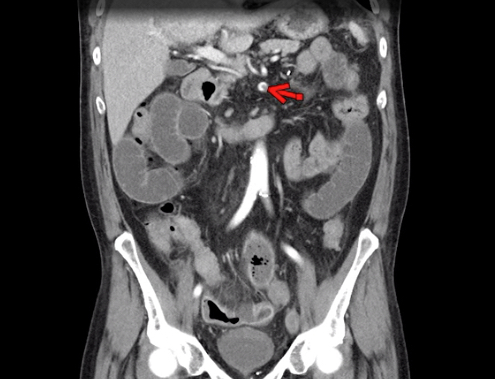

This photo gallery shows the variety of radiological presentations of COVID-19 (SARS-CoV-2) in medical imaging, including computed tomography (CT), radiograph X-rays, ultrasound, echocardiograms and magnetic resonance imaging (MRI). The radiology images show examples of typical COVID pneumonia in the lungs and the numerous complications the virus causes in the body in multiple organs, including the brain, kidneys, heart, abdomen and vascular system.